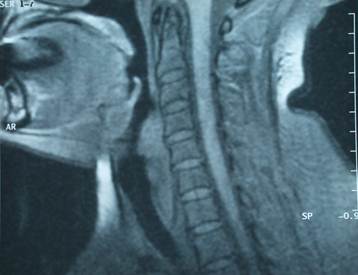

A 52-year-old female patient referred to our clinic with feeling of thickness in the throat, and a mass in the mouth while coughing. She described her complications as having begun 5 or 6 years previously, with a mass appearing in her mouth every time she retched in the last two years. The patient described no occurrence of dysphagia during this period. Her examination revealed a normal oral cavity and oropharynx. Tongue root, vallecula, sinus pyriformis, epiglottis, ventricular folds, and the vocal cords had a normal appearance upon endoscopic examination. However, it was observed that the mass projected up to her teeth when she retched (Figure 1). After the mass was stabilized, endoscopic monitoring revealed it to be smooth surfaced and its origin to be left sinus pyriformis. Preoperative magnetic resonance imaging of the patient revealed a polypoid structure approximately 6 cm long and 5 mm in diameter, corresponding to the laryngeal vestibule level in sagittal section, projecting towards the inferior from the arytenoid cartilage level. It appeared hypointense in T1-weighted sequences, and hyperintense in T2-weighted sequences. Contrast was positive following intravenous contrast administration (Figure 2). The mass was removed surgically by suspension microlaryngoscopy. The resected mass was observed to be yellowish in color; smooth-surfaced, solitary, and well-capsulated (Figure 3). Pathological examination of microscopic sections revealed a multilobular mass, with spindle and star-shaped cells lacking well-defined borders located beneath the squamous epithelium in the myxoid area. No mitosis was observed, while rare giant cells were detected (Figure 4). Angiomyxolipoma was considered initially, yet immunohistochemical analysis was requested for elimination of possible aggressive angiomyxoma and least likely low grade liposarcoma. The immunohistochemical examination revealed diffused immunoexpressions of CD34 and Vimentin. It was negative for CDK4, S-100 and MDM2. No immune expression was detected in the other panels studied. The diagnosis was confirmed as myxoid type spindle cell lipoma. The excision region was monitored as normal at postoperative month 6. The patient was asymptomatic.

Figure 2

Preoperative magnetic resonance imaging (Sagittal section).